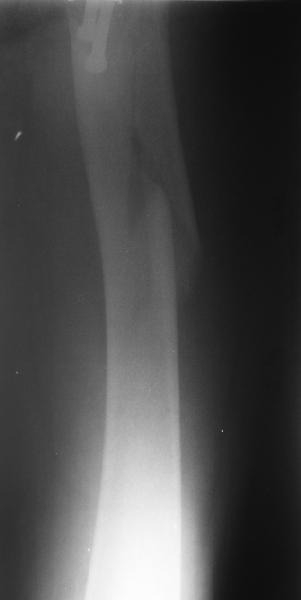

A lateral film would help.

See above for the only one available at the moment.

Еще одна боковая проекция. На сегодня назначен закрытый интрамедуллярный остеосинтез. Реконструкционного гвоздя для этой больной не нашлось, придется делать обычным.

Another lateral view. A closed nailing is scheduled for today. No reconstuction nail is available so a usual one is planned.